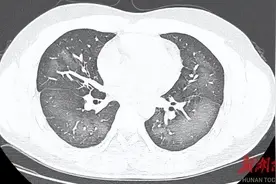

夏天出门,很多人都会拿着防晒喷雾从上到下一通“喷喷喷”。紧急提醒:别对着脸!这次又有人中招了,妈妈看着7岁女儿的胸片报告,后悔都来不及……防晒喷雾对脸喷,7岁女孩不到一天确诊急性过敏性肺炎,已接近“白肺”几天前,趁着暑期的“尾巴”,7岁小女孩涵涵跟着家人来杭州游玩。

趁着暑期的“尾巴”,几天前,7岁小姑娘涵涵跟着家人去杭州游玩。户外艳阳高照,涵涵出门前拿着妈妈的防晒喷雾,对着自己面部喷了又喷。防晒喷雾冰冰凉凉,喷完后,涵涵咳嗽了一两声。资料图出门玩耍没多少时间,涵涵的咳嗽一声连着一声,越来越剧烈,甚至连早饭也咳吐了。